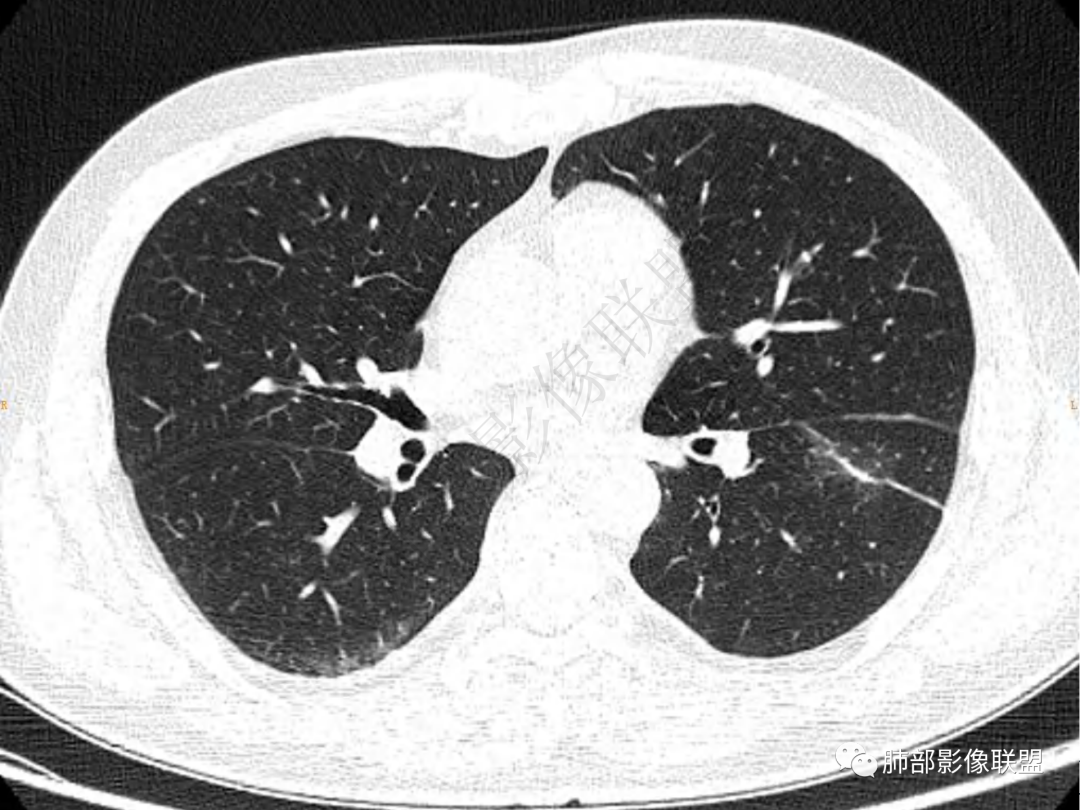

2.左肺下叶团片影,跨背段及内前基底段,实性部分类椭圆形,密度不甚均匀,可见毛刺及棘状突起,未见典型分叶及胸膜凹陷。病灶上下缘可见相应肺段支气管旁进侧出,管壁轻度增厚,未见狭窄阻塞。

3.周边较大范围磨玻璃影,边界相当模糊,小叶增厚明显。注意叶裂另一侧、左肺舌段亦可见磨玻璃影及增厚的小叶间隔。未见明确卫星病灶。

1.病灶不够密实,没有典型分叶,收缩乏力等,支气管未见截断等,缺乏一般肿瘤性肿块特征。

肺脓肿:可宽基底与胸膜相连,附近胸膜增厚——炎性特点

肺脓肿:边界模糊不清,或者块影为类圆形,无明显分叶,边缘平直为主,刀切征——炎性特点三、病灶周围特点:肺脓肿:病灶非远端有片状GGO——炎性特点四、近端支气管阻塞:肺脓肿:常有引流支气管伴管壁增厚或者支气管沿洞壁走行。五:坏死壁:肺脓肿:大多壁厚,少数壁薄,没有壁结节,内壁清楚光整——炎性特点